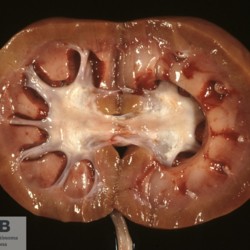

Etiquetes: N-82/88 3 total Ovine Specie: Ovine Organ: Kidney Lesion: Urolithiasis Lesion modifier: - Disease: - Files/Expedient: N-82/88 Position: 253 (1 views) Ovine Specie: Ovine Organ: Urinay bladder Lesion: Cystitis Lesion modifier: Cystitis - Hemorrhagic Disease: - Files/Expedient: N-82/88 Not viewed Ovine Specie: Ovine Organ: Kidney Lesion: Cystitis Lesion modifier: Cystitis - Hemorrhagic Disease: - Files/Expedient: N-82/88 Not viewed Títol Select...Avian (Exotic) (110)Avian (Poultry) (76)Bovine (317)Canine (935)Caprine (47)Equine (257)Feline (326)Ferret (19)General (127)Marine mammal (22)Non-human primate (20)Ovine (328)Porcine (379)Rabbit (61)Reptile (38)Rodent (28)Wildlife (91) Format Select...- (60)Abomasum (37)Adrenal gland (10)Blood (7)Blood vessel (50)Body as a whole (19)Bone (57)Bone marrow (21)Brain (93)Cloaca (1)Diaphragm (2)Ear (5)Esophagus (39)Eye (16)Fetus (12)Gallbladder (23)Gizzard (2)Heart (265)Intestine (356)Joint (32)Kidney (443)Larynx (5)Liver (326)Lung (264)Lymph node (91)Mammary gland (10)Mediastinum (1)Muscle (22)Nasal cavity (22)Nerve (7)Omasum (5)Oral cavity (63)Ovary (14)Oviduct (8)Pancreas (7)Parathyroid (5)Penis (10)Peritoneum (65)Pharynx (9)Pituitary gland (6)Placenta (7)Prostate (8)Proventriculus (3)Reticulum (1)Rumen (28)Sinus (7)Skin (181)Spinal cord (15)Spleen (105)Stomach (125)Teeth (1)Testicle (11)Thoracic cavity (31)Thymus (13)Thyroid gland (5)Tongue (32)Tonsils (11)Trachea (11)Urethra (5)Urinay bladder (61)Uterus (27)Vagina (1)Vulva (1)Yolk sac (1) Cobertura Select...- (152)Abomasitis (26)Abscess (27)Acidosis (1)Adenocarcinoma (20)Adenoma (9)Aerosacculitis (6)Agenesis (1)Agnathia (1)Alopecia (7)Amyloidosis (12)Aneurysm (6)Angiectasis (1)Anthracosis (1)Arteritis (11)Arthritis (15)Arthrogryposis (6)Artifact (4)Ascites (13)Atelectasis (8)Atherosclerosis (5)Atresia (1)Atrial septal defect (2)Atrophy (10)Autolysis (7)Bronchitis (6)Bronchopneumonia (26)Cachexia (2)Carcinoma (103)Cardiomyopathy (19)Cellulitis (2)Chemodectoma (4)Cholangiohepatitis (4)Cholangitis (19)Cholecystitis (4)Cholestasis (5)Chondrodysplasia (2)Chondrosarcoma (2)Chronic passive congestion (13)Chylothorax (2)Cirrhosis (6)Coelomitis (3)Coenurus cerebralis (4)Colitis (40)Congestion (17)Conjunctivitis (5)Coronitis (3)Cryptorchidism (3)Cyst (25)Cystitis (24)Dermatitis (69)Diaphragmatic hernia (4)Dilation (28)Discospondylitis (1)Disseminated intravascular coagulation (7)Dyschondroplasia (1)Dysplasia (29)Ectopia cordis (1)Ectopic ureter (1)Edema (55)Emphysema (5)Encephalitis (5)Endocardiosis (14)Endocarditis (26)Endometritis (5)Enteritis (118)Enterolith (6)Epulis (3)Esophagitis (14)Fasciitis (1)Fibrosis (7)Fibrous osteodystrophy (8)Fistula (1)Folliculitis (3)Fracture (2)Gastritis (34)Gingivitis (5)Glioma (8)Glomerulonephritis (21)Glossitis (25)Glycogenosis (1)Gout (8)Granuloma (2)Granulosa cell tumor (4)Hemangioma (9)Hemangiosarcoma (46)Hematoma (8)Hemoglobinuria (2)Hemopericardium (12)Hemoperitoneum (2)Hemorrhage (100)Hemosiderosis (7)Hemothorax (2)Hepatitis (78)Hernia (11)Histiocytosis (3)Hydatid cyst (11)Hydrocephalus (9)Hydrometra (1)Hydronephrosis (22)Hydropericardium (6)Hydrothorax (3)Hydroureter (5)Hyperkeratosis (8)Hyperostosis (4)Hyperplasia (37)Hypertrophy (9)Hypopigmentation (1)Hypoplasia (7)Hypopyon (1)Impaction (6)Infarction (63)Insulinoma (6)Intussusception (5)Jaundice (17)Laminitis (2)Laryngitis (2)Leiomyoma (5)Leukemia (13)Lipidosis (36)Lipoma (7)Lymphadenitis (45)Lymphadenopathy (7)Lymphangiectasia (6)Lymphangitis (5)Lymphoma (221)Malacia (11)Malignant melanoma (15)Mast cell tumor (11)Mastitis (8)Megaesophagus (2)Melanosis (3)Melena (4)Meningioma (6)Meningitis (6)Meningocele (2)Meningoencephalitis (5)Mesothelioma (5)Methemoglobinemia (2)Mineralization (10)Mucocele (5)Mucometra (1)Multilobular bone tumor (1)Mummification (3)Myelofibrosis (1)Myocarditis (4)Myositis (5)Necrosis (81)Nephritis (113)Nephroblastoma (6)Nephrosclerosis (1)Nephrosis (14)Neuritis (1)Obstruction (13)Omasitis (4)Omphalitis (1)Omphalophlebitis (7)Orchitis (4)Osteoarthrosis (5)Osteomyelitis (9)Otitis (2)Palatoschisis (3)Pancreatitis (3)Panniculitis (3)Papilloma (7)Parakeratosis (14)Patent ductus arteriosus (6)Peliosis hepatis (1)Perforation (17)Pericarditis (35)Peritonitis (39)Persistent right aortic arch (1)Pharyngitis (2)Pheochromocytoma (2)Phlebitis (2)Placentitis (6)Pleuritis (21)Pleuropneumonia (24)Pneumonia (109)Pneumothorax (3)Polycystosis (14)Polyp (5)Polyserositis (6)Posthitis (1)Proctitis (4)Prolapse (3)Prostatitis (3)Proventriculitis (1)Pyelonephritis (24)Pyometra (6)Pyothorax (4)Rhinitis (11)Rumenitis (6)Rupture (24)Salpingitis (3)Sarcoma (57)Sclerosis (1)Scoliosis (2)Seminoma (2)Sequestrum (2)Serous atrophy (14)Sinusitis (7)Splenitis (14)Splenomegaly (9)Spondylitis (6)Spondylosis (1)Stenosis (9)Stomatitis (32)Tenosynovitis (2)Teratoma (3)Thricobezoar (2)Thrombosis (16)Tonsilitis (4)Torsion (13)Tracheitis (4)Tympany (7)Typhlitis (8)Typhlocolitis (4)Ulcer (43)Urethritis (1)Urolithiasis (36)Uroperitoneum (1)Uveitis (1)Vasculitis (15)Ventricular septal defect (3)Volvulus (11) Matèria Select... - (14)- (1653)- (152)Abomasitis - Catarrhal (2)Abomasitis - Catarrhal-hemorrhagic (1)Abomasitis - Chronic (1)Abomasitis - Fibrinous-necrotizing (2)Abomasitis - Hyperplasic (5)Abomasitis - Hyperplasic - Chronic (1)Abomasitis - Necrotic (1)Abomasitis - Necrotizing (2)Abomasitis - Ulcerative (5)Adenocarcinoma (9)Aerosacculitis - Granulomatous (1)Amyloidosis - Chronic (1)Arteritis - Necrotic (2)Arteritis - Necrotizing (1)Arthritis - Chronic (4)Arthritis - Fibrinous-purulent (3)Arthritis - Serous (4)Arthritis - Subacute (1)Ascites - Serous (1)Atrophy - Serous (1)Bronchitis - Catarrhal (3)Bronchitis - Suppurative (1)Bronchopneumonia - Catarrhal-purulent (17)Bronchopneumonia - Fibrinous (1)Bronchopneumonia - Granulomatous (1)Bronchopneumonia - Purulent (1)Bronchopneumonia - Suppurative (5)Carcinoma - Adenocarcinoma (33)Carcinoma - Adenocarcinoma - Hepatocellular (2)Carcinoma - Adenocarcinoma - Mucinous (1)Carcinoma - Basosquamous (1)Carcinoma - Cholangiocellular (3)Carcinoma - Hepatocellular (4)Carcinoma - Metastatic (3)Carcinoma - Squamous cell carcinoma (13)Carcinoma - Transitional cell (2)Cardiomyopathy - Dilated (13)Cardiomyopathy - Hypertrophic (6)Cellulitis - Necrotizing (1)Cholangitis - Chronic (8)Cholangitis - Hyperplasic (3)Cholecystitis - Fibrinous-necrotizing (1)Coelomitis - Fibrinous (1)Coelomitis - Granulomatous (1)Colitis - Catarrhal (3)Colitis - Catarrhal-hemorrhagic (1)Colitis - Fibrinous (1)Colitis - Fibrinous-necrotizing (1)Colitis - Fibrinous-necrotizing (Diphtheritic) (6)Colitis - Granulomatous (2)Colitis - Hemorrhagic (4)Colitis - Hemorrhagic-necrotizing (3)Colitis - Necrotizing (2)Colitis - Ulcerative (6)Congestion - Chronic (2)Conjunctivitis - Hyperplasic (1)Conjunctivitis - Purulent (3)Coronitis - Ulcerative (1)Cystitis - Chronic (3)Cystitis - Fibrinous (1)Cystitis - Fibrinous-necrotizing (1)Cystitis - Follicular (1)Cystitis - Hemorrhagic (6)Cystitis - Hemorrhagic-ulcerative (1)Cystitis - Necrotizing (9)Cystitis - Perforated (1)Dermatitis - Granulomatous (14)Dermatitis - Hyperkeratotic (10)Dermatitis - Hyperplasic (proliferative) (1)Dermatitis - Hyperplastic (10)Dermatitis - Necrotizing (4)Dermatitis - Pustular (4)Dermatitis - Ulcerative (2)Dilation - Chronic (1)Discospondylitis - Necrotizing (1)Dysplasia - Follicular (5)Edema - Interstitial (6)Emphysema - Interstitial (1)Encephalitis - Granulomatous (1)Encephalitis - Nonsuppurative (1)Endocardiosis - Mitral (7)Endocardiosis - Mitral - Chronic (5)Endocarditis - Valvular (6)Endocarditis - Valvular - Mitral (7)Endocarditis - Valvular - Pulmonic (1)Endocarditis - Valvular - Subacute (1)Endocarditis - Valvular - Subaortic (5)Endocarditis - Valvular - Tricuspid (4)Endometritis - Purulent (3)Endometritis - Purulent-hemorrhagic (2)Enteritis - Catarrhal (23)Enteritis - Catarrhal - Acute (1)Enteritis - Catarrhal-hemorrhagic (5)Enteritis - Catarrhal-hemorrhagic - Acute (2)Enteritis - Fibrinous (16)Enteritis - Fibrinous - Acute (3)Enteritis - Fibrinous-necrotizing (7)Enteritis - Granulomatous (14)Enteritis - Granulomatous - Chronic (1)Enteritis - Granulomatous - Multifocal (1)Enteritis - Hemorrhagic (17)Enteritis - Hemorrhagic - Acute (1)Enteritis - Hemorrhagic-necrotizing (1)Enteritis - Hyperplasic (proliferative) (4)Enteritis - Necrotizing (4)Enteritis - Necrotizing - Acute (1)Enteritis - Necrotizing - Hemorrhagic (1)Enteritis - Necrotizing-ulcerative (2)Enteritis - Ulcerative (1)Enteritis - Ulcerative-hemorrhagic (1)Esophagitis - Erosive-ulcerative (6)Esophagitis - Necrotizing (4)Esophagitis - Ulcerative (1)Esophagitis - Ulcerative-necrotizing (1)Fasciitis - Fibrinous-purulent (1)Folliculitis - Purulent (2)Gastritis - Catarrhal (2)Gastritis - Chronic (1)Gastritis - Follicular (1)Gastritis - Hemorrhagic (2)Gastritis - Hemorrhagic-necrotizing (1)Gastritis - Hypertrophic (2)Gastritis - Inclusion bodies (1)Gastritis - Mineralization (1)Gastritis - Mycotic (1)Gastritis - Necrotizing (2)Gastritis - Ulcerative (6)Gastritis - Uremic (3)Gingivitis - Erosive (2)Gingivitis - Hyperplasic (proliferative) (1)Gingivitis - Necrotizing (1)Glomerulonephritis - Chronic (7)Glomerulonephritis - Membranoproliferative (3)Glomerulonephritis - Membranoproliferative - Chronic (1)Glomerulonephritis - Membranous (3)Glomerulonephritis - Membranous - Chronic (1)Glomerulonephritis - Proliferative (2)Glomerulonephritis - Subacute (1)Glossitis - Erosive (2)Glossitis - Granulomatous (6)Glossitis - Hyperplasic (1)Glossitis - Hyperplasic (proliferative) (2)Glossitis - Hyperplastic (1)Glossitis - Necrotizing (2)Glossitis - Necrotizing - Focal (1)Glossitis - Ulcerative (6)Glossitis - Ulcerative - Multifocal (1)Glossitis - Ulcerative - Subacute (1)Glycogenosis (1)Granuloma - Eosinophilic (1)Hemangiosarcoma - Metastatic (2)Hemorrhage - Acute (1)Hemorrhage - Subcapsular (3)Hepatitis - Abscess (9)Hepatitis - Acute (3)Hepatitis - Chronic (4)Hepatitis - Chronic interstitial (6)Hepatitis - Granulomatous (7)Hepatitis - Interstitial - Multifocal (1)Hepatitis - Interstitial - Subacute (1)Hepatitis - Necrotizing (17)Hepatitis - Necrotizing - Acute (2)Hepatitis - Necrotizing - Hemorrhagic (1)Hepatitis - Necrotizing - Subacute (1)Hepatitis - Pyogranulomatous (7)Hepatitis - Subacute (4)Hydronephrosis - Chronic (1)Hydropericardium - Chronic (1)Hyperplasia - Erythroid (1)Hyperplasia - Lymphoid (3)Hyperplasia - Myeloid (1)Hyperplasia - Nodular (8)Hypertrophy - Concentric (2)Hypertrophy - Eccentric (3)Infarction - Acute (17)Infarction - Acute - Multifocal (2)Infarction - Chronic (5)Infarction - Chronic - Multifocal (1)Infarction - Subacute (18)Infarction - Subacute - Focal (2)Laminitis - Chronic (2)Laryngitis - Necrotic (1)Laryngitis - Necrotizing (1)Leukemia - Lymphoid leukemia (2)Leukemia - Non-lymphoid leukemia (6)Lipidosis - Multifocal (1)Lipidosis - Panlobular (1)Lipidosis - Panlobular - Generalized (2)Lymphadenitis - Granulomatous (24)Lymphadenitis - Granulomatous - Chronic (3)Lymphadenitis - Hemorrhagic (1)Lymphadenitis - Necrotizing (5)Lymphadenitis - Necrotizing (caseous) (11)Lymphangitis - Granulomatous (1)Lymphangitis - Purulent (1)Lymphangitis - Ulcerative (1)Lymphoma - Alimentary lymphoma (7)Lymphoma - Cutaneous lymphoma (6)Lymphoma - Lymphosarcoma (2)Lymphoma - Mediastinal lymphoma (1)Lymphoma - Multicentric lymphoma (29)Malignant melanoma - Malignant (1)Malignant melanoma - Metastatic (1)Mast cell tumor - Metastatic (1)Mastitis - Fibrinous-purulent (2)Mastitis - Necrotic (1)Mastitis - Purulent (3)Mastitis - Suppurative (1)Meningitis - Fibrinous-purulent (2)Meningitis - Purulent (4)Meningoencephalitis - Necrotizing (3)Meningoencephalitis - Nonsuppurative (2)Mineralization - Metastatic (4)Myocarditis - Fibrous - Chronic (1)Myocarditis - Granulomatous (1)Myositis - Purulent (2)Necrosis - Acute (1)Necrosis - Cortical (5)Necrosis - Follicular (1)Necrosis - Papillary (8)Necrosis - Papillary - Acute (3)Necrosis - Subacute (3)Necrosis - Tubular (6)Nephritis - Embolic (2)Nephritis - Embolic suppurative (7)Nephritis - Granulomatous (27)Nephritis - Granulomatous - Chronic (1)Nephritis - Granulomatous - Multifocal (1)Nephritis - Interstitial (6)Nephritis - Interstitial - Acute (4)Nephritis - Interstitial - Chronic (41)Nephritis - Interstitial - Subacute (12)Nephritis - Purulent (7)Nephritis - Purulent - Acute (2)Nephritis - Purulent - Multifocal (3)Nephrosis - Cholemic (3)Nephrosis - Hemoglobinuric (10)Omasitis - Fibrinous-necrotizing (1)Omasitis - Hyperkeratotic (1)Omasitis - Necrotizing (2)Omphalophlebitis - Fibrinous-purulent (2)Omphalophlebitis - Purulent (3)Orchitis - Necrotizing (1)Osteomyelitis - Necrotizing (7)Osteomyelitis - Purulent (2)Otitis - Necrotizing (1)Otitis - Proliferative (1)Pancreatitis - Acute (1)Pancreatitis - Chronic (1)Pancreatitis - Granulomatous (1)Panniculitis - Fibrinous-purulent (1)Panniculitis - Necrotic (1)Panniculitis - Parasitic (1)Perforation - Acute (2)Pericarditis - Fibrinous (19)Pericarditis - Fibrinous - Subacute (1)Pericarditis - Fibrinous-necrotizing (1)Pericarditis - Fibrinous-purulent (3)Pericarditis - Fibrous (1)Pericarditis - Fibrous - Chronic (1)Pericarditis - Gangrenous (6)Pericarditis - Granulomatous (1)Pericarditis - Granulomatous - Chronic (2)Peritonitis - Acute (1)Peritonitis - Fibrinous (11)Peritonitis - Fibrinous - Subacute (1)Peritonitis - Fibrinous-purulent (5)Peritonitis - Fibrous (3)Peritonitis - Granulomatous (6)Peritonitis - Purulent (1)Peritonitis - Purulent-hemorrhagic (1)Peritonitis - Pyogranulomatous (3)Pharyngitis - Fibrinous-necrotizing (1)Pharyngitis - Ulcerative (1)Pheochromocytoma - Metastatic (1)Phlebitis - Purulent (1)Placentitis - Fibrinous-necrotizing (1)Placentitis - Necrotic (1)Placentitis - Necrotizing (1)Pleuritis - Chronic (1)Pleuritis - Fibrinous (3)Pleuritis - Fibrinous-purulent (2)Pleuritis - Fibrous (2)Pleuritis - Granulomatous (3)Pleuritis - Hyperplastic (2)Pleuritis - Purulent (2)Pleuritis - Pyogranulomatous (1)Pleuropneumonia - Fibrinous (13)Pleuropneumonia - Fibrinous-necrotizing (5)Pleuropneumonia - Granulomatous (2)Pleuropneumonia - Hemorrhagic-necrotizing (4)Pneumonia - Aspiration (11)Pneumonia - Bronchointerstitial (4)Pneumonia - Bronchointerstitial - Subacute (1)Pneumonia - Embolic (5)Pneumonia - Granulomatous (37)Pneumonia - Granulomatous - Multifocal (4)Pneumonia - Hemorrhagic-necrotizing (2)Pneumonia - Interstitial (7)Pneumonia - Interstitial - Acute (8)Pneumonia - Interstitial - Chronic (6)Pneumonia - Interstitial - Subacute (15)Pneumonia - Necrotizing (2)Pneumonia - Pyogranulomatous (2)Pneumonia - Verminous (5)Polyserositis - Fibrinous (6)Polyserositis - Fibrous (1)Proctitis - Fibrinous-necrotizing (1)Proctitis - Parasitic (2)Prostatitis - Purulent (1)Pyelonephritis - Acute (2)Pyelonephritis - Chronic (3)Rhinitis - Catarrhal (2)Rhinitis - Fibrinous (1)Rhinitis - Granulomatous (4)Rhinitis - Purulent (3)Rumenitis - Acute (1)Rumenitis - Erosive (1)Rumenitis - Necrotizing (1)Rupture - Acute (3)Sarcoma - Fibrosarcoma (12)Sarcoma - Hemangiosarcoma (11)Sarcoma - Histiocytic (7)Sarcoma - Metastatic (1)Sarcoma - Multilobular tumor of bone (1)Sequestrum - Chronic (2)Sinusitis - Suppurative (1)Splenitis - Granulomatous (8)Splenitis - Granulomatous - Chronic (1)Splenitis - Necrotizing (3)Splenitis - Necrotizing (caseous) (2)Spondylitis - Necrotizing (2)Stenosis - Intestinal (1)Stenosis - Valvular - Subaortic (4)Stomatitis - Erosive (12)Stomatitis - Erosive-ulcerative (3)Stomatitis - Fibrinous-necrotizing (1)Stomatitis - Fibrinous-necrotizing (Diphtheritic) (1)Stomatitis - Granulomatous (1)Stomatitis - Hyperplasic (1)Stomatitis - Hyperplasic (proliferative) (1)Stomatitis - Necrotizing (2)Stomatitis - Ulcerative (5)Stomatitis - Ulcerative - Multifocal (1)Stomatitis - Ulcerative-necrotizing (1)Tonsilitis - Necrotizing (4)Torsion - Acute passive hyperemia (5)Tracheitis - Catarrhal (3)Tracheitis - Fibrinous (1)Tracheitis - Granulomatous (1)Typhlitis - Catarrhal (1)Typhlitis - Fibrinous-necrotizing (2)Typhlitis - Hemorrhagic (2)Typhlitis - Ulcerative-hemorrhagic (1)Typhlocolitis - Fibrinous-necrotizing (2)Typhlocolitis - Proliferative (1)Ulcer - Chronic (6)Ulcer - Multifocal (2)Ulcer - Mycotic (1)Ulcer - Perforated (6)Urethritis - Hemorrhagic (1)Urolithiasis - Chronic (2)Uveitis - Granulomatous (1)Vasculitis - Granulomatous (1)Vasculitis - Necrotizing (1) Editor Select...- (1970)Acidosis (2)Actinobacillosis (Pleuropneumonia) (11)Aelurostrongylosis (2)African horse sickness (13)African swine fever (14)Alopecia X (1)Anaplasmosis (4)Anthrax (2)Aortic thromboembolism (feline) (7)Ascariasis (15)Aspergillosis (18)Atopic dermatitis (1)Atrophic rhinitis (3)Babesiosis (6)Blackhead (1)Bluetongue (11)Border disease (2)Bovine viral diarrhea (21)Brucellosis (2)Candidiasis (5)Canine distemper (14)Caprine arthritis-encephalitis (2)Capture myopathy (1)Cardiac insufficiency (17)Caseous lymphadenitis (7)Chlamydiosis (2)Classical swine fever (19)Clostridiosis (19)Coccidiosis (9)Coenurosis (4)Colibacillosis (21)Contagious ecthyma (7)Copper toxicosis (11)Cowdriosis (Heartwater) (3)Cryptococcosis (3)Cryptosporidiosis (2)Cysticercosis (23)Demodicosis (1)Diabetes (1)Dicrocoeliosis (5)Dictyocaulosis (4)Dirofilariasis (7)Discoid lupus erythematosus (3)Echinococcosis (17)Edema disease (7)Egg drop syndrome (1)Encephalitozoonosis (5)Enterotoxemia (1)Enzootic bovine leukosis (46)Epitheliogenesis imperfecta (3)Equine rhinopneumonitis (2)Equine verminous arteritis (strongylosis) (7)Erysipelas (5)Exudative epidermitis (7)Fasciolasis (11)Feline eosinophilic dermatoses (1)Feline hepatic lipidosis (8)Feline histiocytosis (4)Feline infectious peritonitis (38)Feline leukemia (4)Feline lower urinary tract disease (3)Feline panleukopenia (16)Feline viral rhinotracheitis (1)Flea allergy dermatitis (1)Foot and mouth disease (2)Gasterophilosis (4)Glasser's disease (15)Gousiekte (4)Gout (6)Haemonchosis (9)Hemolytic anemia (4)Hemorrhagic diathesis (1)Hepatic insufficiency (11)Hepatosis dietetica (7)Herpesvirosis (6)Hyperadrenocorticism (7)Hyperparathyroidism (10)Hypertrophic osteopathy (6)Hypervitaminosis D (1)Hypodermosis (1)Inclusion body hepatitis (4)Infectious bovine rhinotracheitis (5)Infectious bronchitis (5)Infectious canine hepatitis (13)Influenza (4)Juvenile nephropathy (8)Lamb dysentery (4)Leishmaniasis (28)Leptospirosis (1)Leukosis (5)Listeriosis (4)Lumpy skin disease (3)Maedi-visna (4)Malignant catarrhal fever (12)Mange (6)Mannheimiosis (5)Marek's disease (7)Metabolic bone disease (2)Mucoid enteropathy (5)Mulberry heart disease (5)Myasis (1)Mycobacteriosis (22)Mycosis fungoides (6)Myxomatosis (3)Necrobacillosis (5)Neonatal isoerythrolysis (6)Nocardiosis (4)Oestrosis (2)Onchocerciasis (1)Osteochondrosis (1)Ostertagiosis (6)Ovine pulmonary adenocarcinoma (5)Oxyuriasis (1)Pacheco's disease (4)Papillomatosis (6)Paratuberculosis (18)Parvovirosis (17)Pasteurellosis (11)Pemphigus foliaceus (1)Periodontal disease (1)Polioencephalomalacia of ruminants (4)Polyarteritis nodosa (3)Polycystic kidney disease (13)Porcine circovirosis (11)Porcine dermatitis and nephropathy syndrome (9)Porcine proliferative enteropathy (4)Porcine reproductive and respiratory syndrome (6)Porcine stress syndrome (1)Pox (13)Pregnancy toxemia (3)Proventricular dilatation disease (2)Pseudotuberculosis (yersiniosis) (2)Psittacine beak and feather disease (PBFD) (5)Pyoderma (4)Q fever (4)Rabbit hemorrhagic disease (2)Renal insufficiency (12)Reticuloendotheliosis (2)Rhodococcosis (1)Rickets (1)Rinderpest (2)Salmonellosis (34)Sarcosporidiosis (2)Schmallenberg (7)Septicemia (23)Spirocercosis (11)Streptococcosis (5)Strongylosis (1)Swine dysentery (5)Systemic coronavirosis (5)Tetralogy of Fallot (5)Theileriosis (13)Thromboembolism (5)Toxoplasmosis (11)Transmissible viral proventriculitis (1)Traumatic reticuloperitonitis (3)Traumatism (16)Tuberculosis (58)Ulcerative lymphangitis (1)Uremic syndrome (20)Viral arthritis (6)White muscle disease (9)Wobbler syndrome (2)Xanthomatosis (1)Zygomycosis (4) Idioma Select...- (1180)Bacterial (501)Degeneration (106)Fungal (46)Hemodynamic (112)Idiopathic (22)Inflammation (58)Malformation (88)Neoplasia (343)Nutritional (41)Parasitic (243)Physical/Chemical (93)Toxic (44)Viral (304) Ítem destacat Canine Puppy. Corneal edema